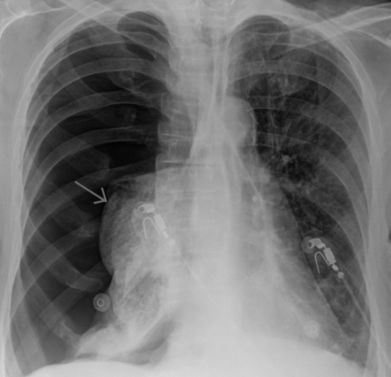

- рентгенография органов грудной клетки;

- рентгенографию;

- рентгенографии грудной клетки;